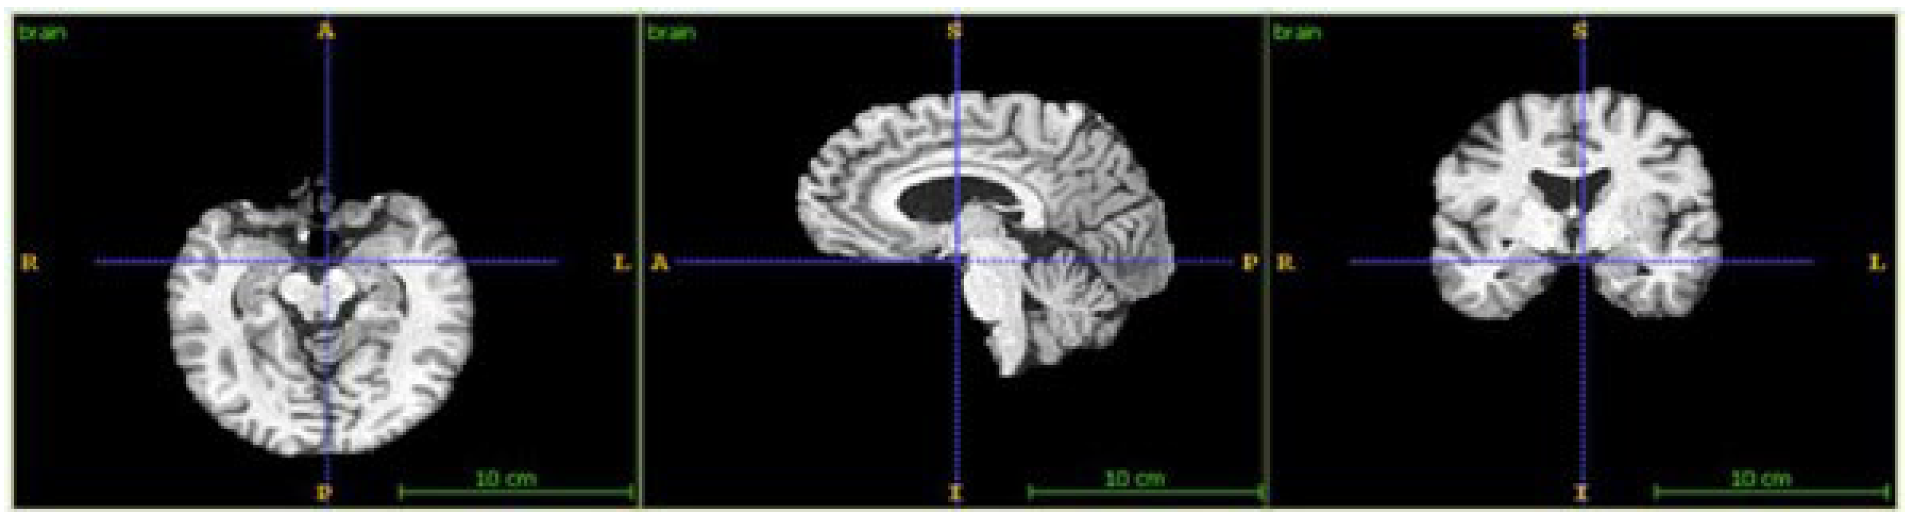

3.2. Image Fusing and Preprocessing

4.3.1. Image Fusion Performance